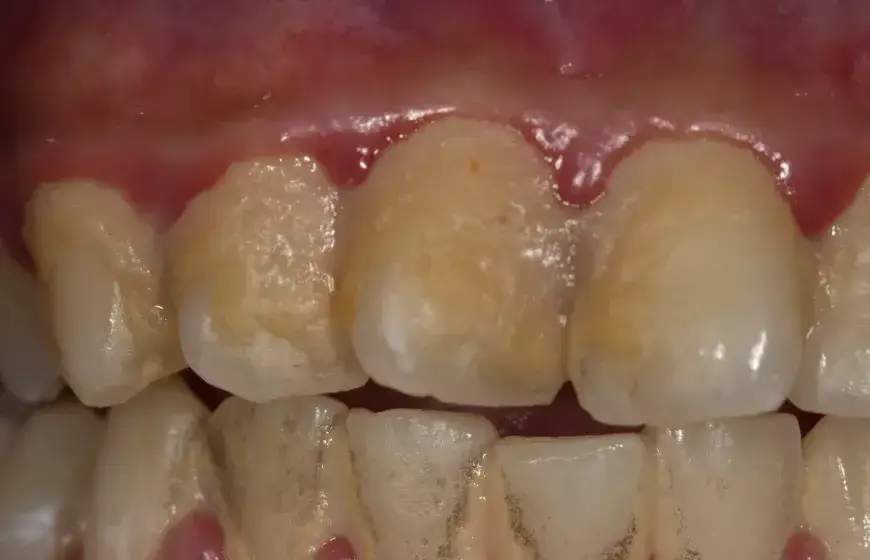

Związek mefedronu z chorobami dziąseł i infekcjami

Mefedron ma również związek z chorobami dziąseł oraz infekcjami w jamie ustnej. Użytkownicy tej substancji mogą doświadczać zapalenia dziąseł, co prowadzi do ich osłabienia i zwiększa ryzyko infekcji. Zmiany w mikroflorze jamy ustnej, spowodowane przez mefedron, mogą sprzyjać rozwojowi bakterii patogennych, które są odpowiedzialne za choroby dziąseł. Objawy zapalenia dziąseł obejmują krwawienie, obrzęk oraz ból, co może znacząco wpłynąć na komfort życia użytkowników.

Badania wykazały, że osoby używające mefedronu mają wyższe ryzyko wystąpienia chorób periodontalnych, które mogą prowadzić do poważniejszych komplikacji zdrowotnych. Na przykład, w badaniu opublikowanym w "Clinical Oral Investigations" zauważono, że użytkownicy mefedronu mieli o 50% większe prawdopodobieństwo wystąpienia chorób dziąseł w porównaniu do osób niezażywających tej substancji. To podkreśla konieczność monitorowania zdrowia jamy ustnej wśród osób używających mefedronu.